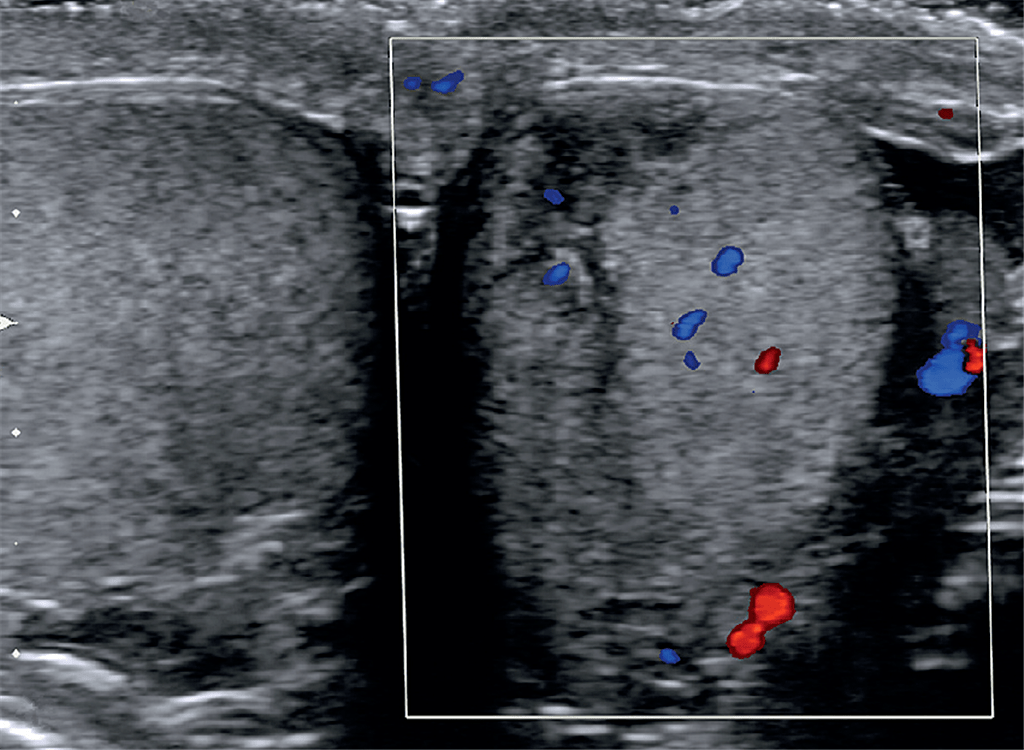

睾丸挫伤一例.

图片尺寸768x576